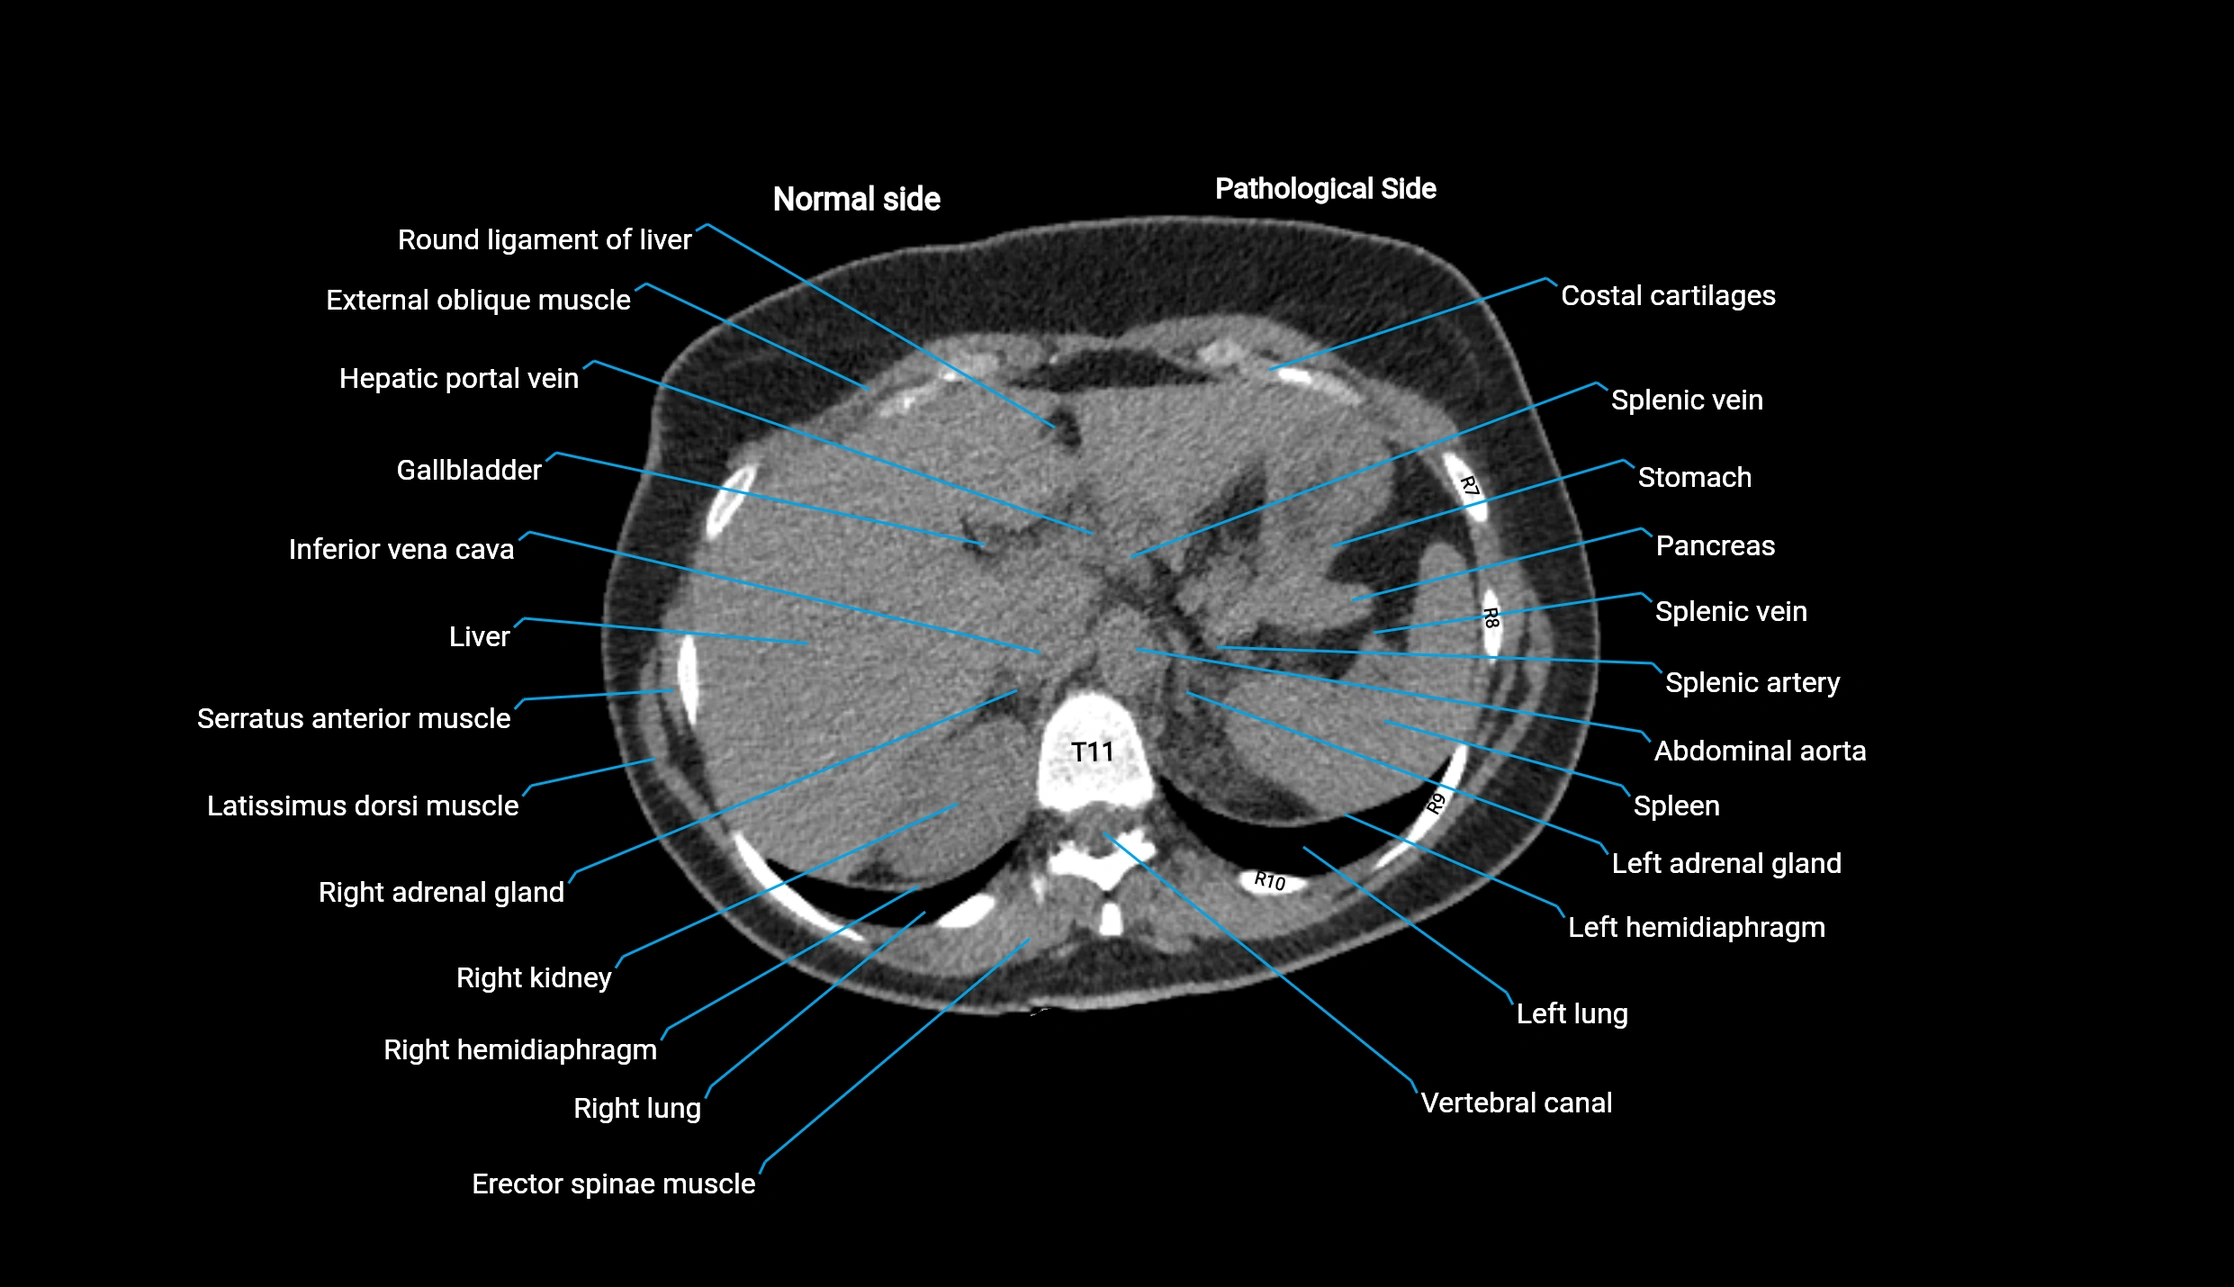

CT image

image